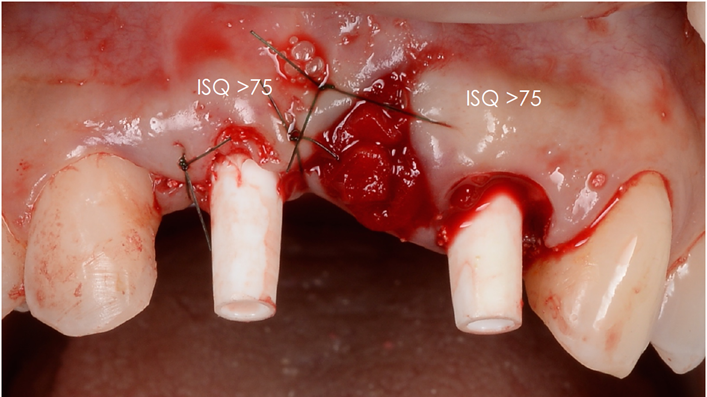

“AnyRidge is perfect for the anterior esthetic zone due to its strong initial stability & fast osseointegration.

Plus, KnifeThread® ensures space maintenance when using the PET/Socket Shield/Root Membrane Technique, showing excellent bone growth.”

Clinical case: Patient-centered approach: treatment strategy for Root Membrane Technique & delayed implant placement

- Courtesy of Dr. Yoshiharu Hayashi, Japan -

Socket Shield Technique, anterior esthetics, maxillary anterior, esthetic, esthetics, delayed implant placement, socket preservation, AnyRidge, Root Membrane Kit, Root Membrane Technique, Partial Extraction Therapy, PET, esthetic zone, fuse abutment, Dr. Yoshiharu Hayashi,#11,#21,#22

Products:

AnyRidge implant system, fuse abutment Root membrane kit, PET Kit